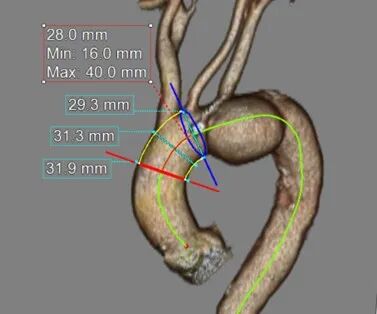

术前3D重建

测量数据:

斑马导丝是治疗什么的「胸有乾坤」至简至易 行之有效—— Zone 0 TBE植入治疗弓部动脉瘤病例报道_https://www.jmylbn.com_新闻资讯_第8张

近端锚定区直径

斑马导丝是治疗什么的「胸有乾坤」至简至易 行之有效—— Zone 0 TBE植入治疗弓部动脉瘤病例报道_https://www.jmylbn.com_新闻资讯_第9张

无名动脉直径

斑马导丝是治疗什么的「胸有乾坤」至简至易 行之有效—— Zone 0 TBE植入治疗弓部动脉瘤病例报道_https://www.jmylbn.com_新闻资讯_第10张

远端锚定区直径.

斑马导丝是治疗什么的「胸有乾坤」至简至易 行之有效—— Zone 0 TBE植入治疗弓部动脉瘤病例报道_https://www.jmylbn.com_新闻资讯_第11张

双侧入路直径